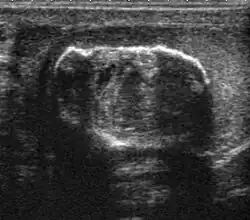

Epididymo-orchitis in a 77-year-old man. (a) Transverse sonography shows enlargement of the epididymis with hypoechogenicity noted over the testis and epididymis associated with scrotal wall thickening. (b) Color Doppler sonography showed hyperemic change of the testis and epididymis, presenting as an “inferno” vascular flow pattern.

Epididymitis and epididymo-orchitis are common causes of acute scrotal pain in adolescent boys and adults. At physical examination, they usually are palpable as tender and enlarged structures. Clinically, this disease can be differentiated from torsion of the spermatic cord by elevation of the testes above the pubic symphysis. If scrotal pain decreases, it is more likely to be due to epidiymitis rather than torsion (Prehn's sign). Most cases of epididymitis are secondary to sexually transmitted disease or retrograde bacteria infection from the urinary bladder.[6] The infection usually begins in the epididymal tail and spreads to the epididymal body and head. Approximately 20% to 40% of cases are associated with orchitis due to direct spread of infection into the testis.

At ultrasound, the findings of acute epididymitis include an enlarged hypoechoic or hyperechoic (presumably secondary to hemorrhage) epididymis [Fig. 20a]. Other signs of inflammation such as increased vascularity, reactive hydrocele, pyocele and scrotal wall thickening may also be present. Testicular involvement is confirmed by the presence of testicular enlargement and an inhomogeneous echotexture. Hypervascularity on color Doppler images [Fig. 20b] is a well-established diagnostic criterion and may be the only imaging finding of epididymo-orchitis in some men.